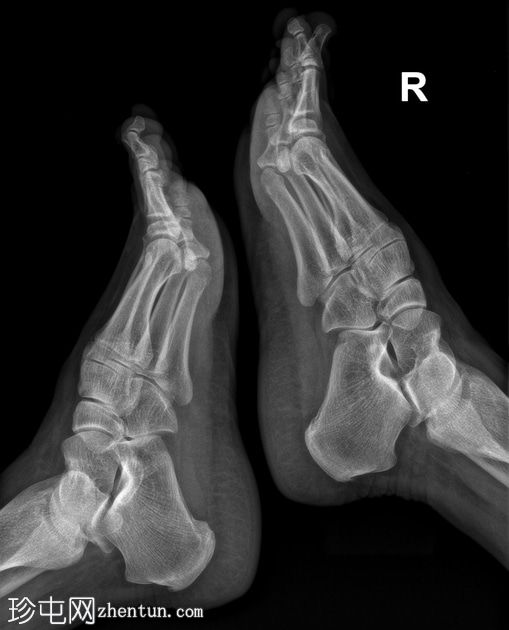

正位片

3.jpg

侧位片

双侧第一跖趾关节周围可见关节外穿凿样边缘性骨侵蚀。